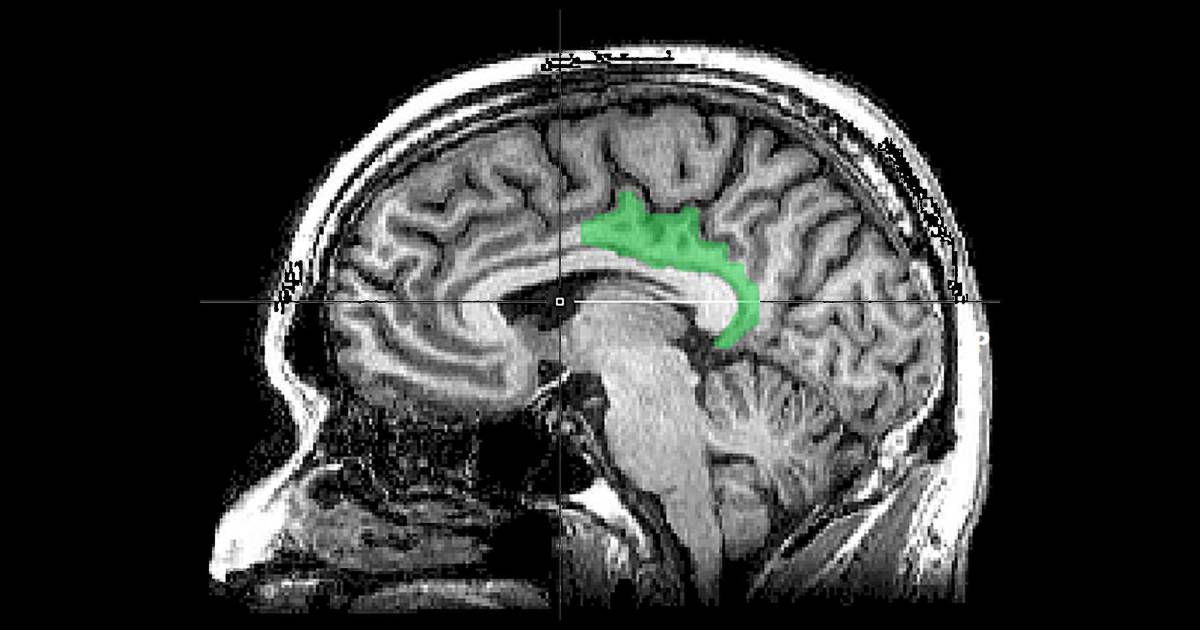

Una imagen de escáner cerebral resalta la corteza cingulada posterior.

Los recuerdos traumáticos parecían involucrar un área distinta del cerebro —la corteza cingulada posterior, o CCP, que por lo general está involucrada en el pensamiento internamente dirigido, como la introspección o soñar despiertos. No se conoce como una región de la memoria. Entre más severos eran los síntomas de TEPT de la persona, más actividad aparecía en la CCP.